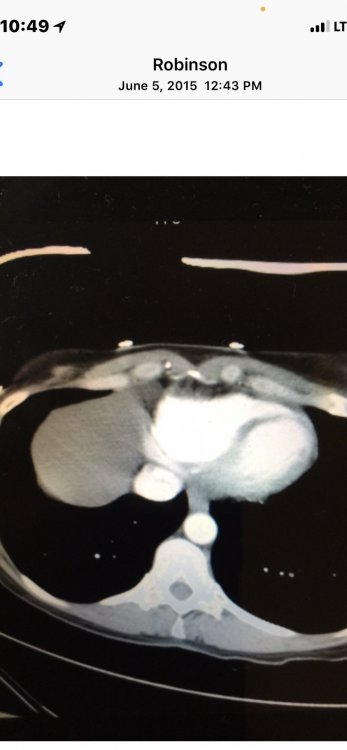

2. That is my exact issue, I’m not a fan of the high proof bourbons. I typically drink bourbon OTR or neat, maybe I need to let it sit for a minute and let some ice melt.

Everything posted by RMac5